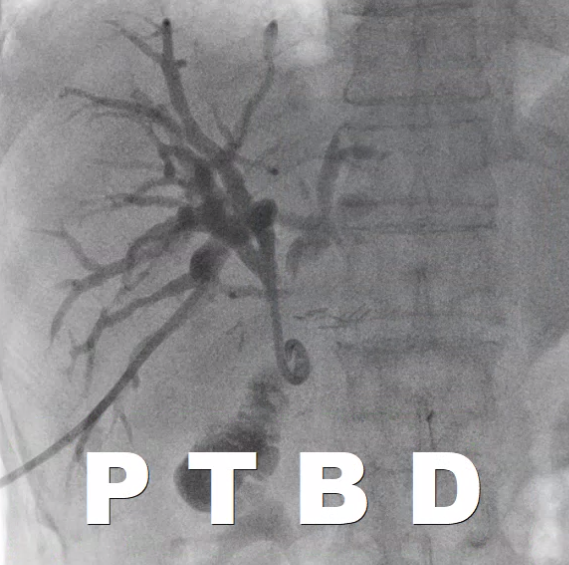

이렇게 늘어나 있는 간내담관을 초음파와 엑스레이 장비를 이용해서 바늘로 찌르고, 배액관을 삽입하는 시술이 경피경간담즙배액술(PTBD)입니다.

혈관조영실에서 초음파와 엑스레이 장비를 이용해서 진행하게 됩니다.

초음파로 늘어난 간내담관을 확인합니다.

위에 제가 올린 CT 처럼 간내담관이 아주 늘어난 경우에는 초음파로도 담관이 잘 보입니다.

초음파로도 잘 보이는 경우에는 초음파를 보고 바늘로 담관을 찌릅니다.

해부학적 지식을 이용해서 엑스레이 장비를 이용해서 간내담관 천자를 시도합니다. (경우에 따라선 매우 여러번 찌를 수도 있습니다. 정말 어쩔 수 없는 부분입니다.)

간내담관 천자에 성공했다면 반 이상은 끝난 겁니다

바늘을 통해 와이어를 넣고, 와이어를 따라서 배액관이 들어갑니다.

이런 돼지 꼬리 모양의 카테터를 넣어 배액관이 잘 빠지지 않게끔 해줍니다. (이름도 돼지 꼬리 입니다.)